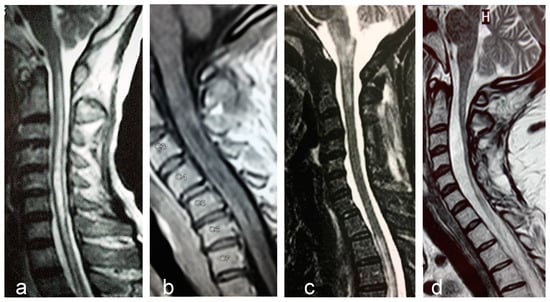

2.6. Magnetic Resonance Imaging